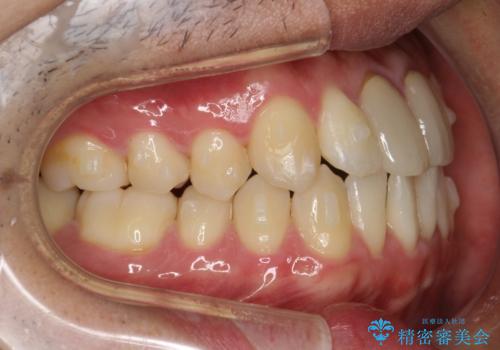

上下のがたつきをインビザラインで目立たない矯正

- 前歯のガタガタを主訴に来院されました。

上下の前歯のガタガタと左上の歯が反対にかんでいる状態でした。

上下の歯と歯の間をわずかに削り並べる計画としました。

目立たずに歯並びがよくなり、前歯に装着されたセラミックも壊さずに矯正治療が終了し満足していただけました。